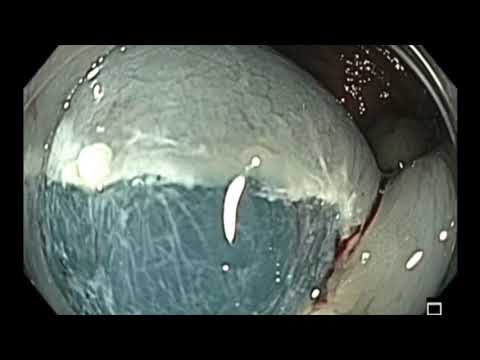

Kolonoskopia: mukozektomia endoskopowa (EMR)...

W filmie pokazano mukozektomię endoskopową (EMR) polipa odbytnicy. Polipa usunięto w całości. Najważniejszą częścią zabiegu EMR jest odpowiednie wstrzyknięcie podśluzówkowe NaCl umożliwiające właściwe...